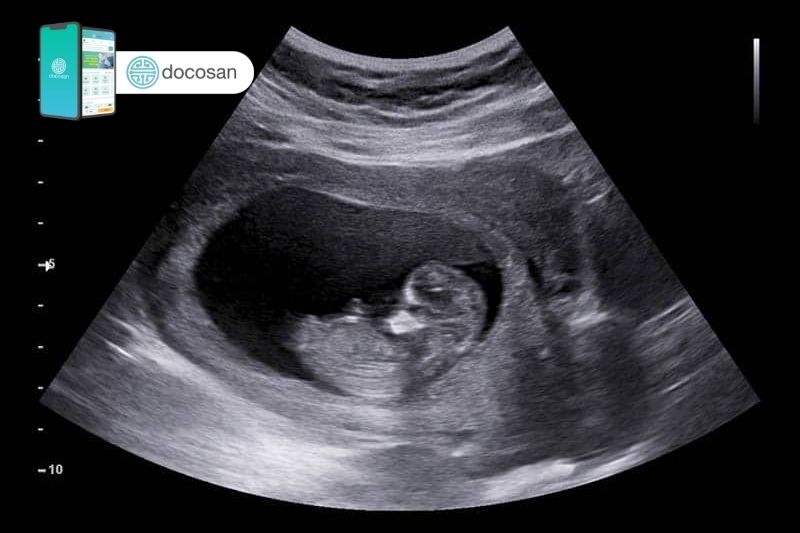

Siêu âm 3D là phương pháp siêu âm 3 chiều, với nhiều góc độ khác nhau và nhất là cùng lúc có thể chụp rất nhiều hình ảnh rồi xử lý lại thành hình ảnh 3D rõ nét. Siêu âm 3D không những quan sát được nội tạng và mô của thai nhi, mà còn thấy rõ được khuôn mặt và nét vóc dáng của thai nhi. Siêu âm 3D còn hiển thị một chuỗi các hình ảnh, cho phép cha mẹ có thể thấy con mình mỉm cười, di chuyển bàn tay và bàn chân hoặc mút ngón tay.

Siêu âm 4D là phương pháp có 3 chiều không gian và kết hợp thêm 1 chiều thời gian. Với công nghệ của máy siêu âm này thì các mẹ bầu có thể nhìn thấy mặt mũi, chân tay, các cử chỉ hành động của thai nhi một cách chân thật nhất. Nhờ đó, bác sĩ có thể phát hiện rõ được ra những dị tật thai nhi giai đoạn sớm, xác định nguy cơ bất thường để có những xử lý kịp thời đảm bảo cho sự phát triển của thai nhi và sức khỏe sản phụ.

Siêu âm 3D và siêu âm 4D còn hiển thị cả da bên ngoài của trẻ, tay chân và các cơ quan của cơ thể thai nhi mà siêu âm 2D không thấy được. Tuy nhiên, không phải lúc nào các hình ảnh cũng luôn luôn hoàn hảo mà đôi khi có thể mờ, mỏng hoặc bóp méo do tư thế thai nhi hoặc gặp vấn đề với thiết bị. Trong trường hợp này không có nghĩa là em bé có vấn đề gì về dị tật thai nhi mà cần theo dõi thêm ở lần siêu âm sau đó.